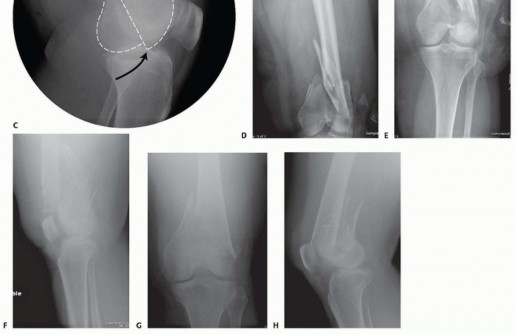

### FIG 11 • (continued) G,H. Five-month follow-up films showing replacement of the calcium sulfate beads with successful consolidation of the metaphyseal comminution. The flexibility of fixation constructs can be increased by the use of a technique referred to as far cortical locking. Specialized screws are used, in which the screw locks into the plate and only engages the far cortex. This has been thought to improve fracture healing. 5 The “polyaxial” locking plates have been shown to be biomechanically sound in the management of supracondylar femur fractures. 12, 18 ## Preoperative Planning Surgical timing can be affected by the following: Soft tissue issues Medical condition of the patient Adequacy of available operative team Availability of implants The approach must take the following issues into consideration: The ability to incorporate lacerations in open fractures into the incision ( FIG 13) can be useful and should be considered. However, this is not always necessary or possible.

### FIG 15 • A. C-arm view of the uninjured knee with patella-forward facing. B. This is followed by imaging of the ipsilateral hip to obtain the lesser trochanter profile (outlined). A similar profile should be recreated on the injured side with the hip bum C. Positioning of the C-arm relative to the flexed knee to obtain a notch view to evaluate for guide pin penetration in the posterior aspect. D. The resulting C-arm image. A notch view is useful for screw trajectories in the distal femur. This is achieved by the C-arm angled roughly around 30 to 45 degrees directed cephalad and visualization will depend on the concurrent amount of knee flexion ( FIG 15C,D). ## Approach The best-known approach for the treatment of distal femur fractures has been the straight lateral approach ( FIG 16). This is suitable for all fracture types, mostly types A and C1. The incision may curve distally toward the tibial tubercle, and osteotomy may be performed. Newer approaches include a lateral inverted U to allow better access to the joint and to allow for plate placement. The minimally invasive lateral approach can be used for certain fractures and implants. The joint must be visualized, reduced, and stabilized. The placement of the plate on the shaft is done submuscularly, and reduction and fixation are done percutaneously under fluoroscopic guidance. This is ideal for the LISS plate or plating system with targeting devices for the screws in the plate. A modified anterior approach (the swashbuckler) has been described by Starr et al. 16 This involves a midline incision. A lateral parapatellar arthrotomy is done with elevation of the vastus lateralis as in the lateral approach.

--- - FIG 16 • Skin incision for a lateral approach. 478 A medial parapatellar arthrotomy can be used for retrograde intramedullary nailing or limited screw fixation. Miniarthrotomy is used for the retrograde nail. Type B injuries may require a formal arthrotomy. A medial approach has been described. This is appropriate for types B2 and B3 fractures. It can be used in type C3 fractures if a second plate is being used (in conjunction with a lateral approach). A total knee approach has been described by Schatzker. 15 This is extremely helpful for type C2 or C3 fractures. It is used for plates but can be used for retrograde intramedullary nailing once the articular surface is reconstructed. A midline approach is used. An extended medial parapatellar arthrotomy is done. This allows exposure of the condyles for articular reduction. A midline incision with a lateral parapatellar arthrotomy is my preferred exposure for type C2 or C3 fractures. A midline approach is used. A lateral parapatellar arthrotomy is done. Proximal extension is made into the quadriceps tendon, enough to repair to itself. Medial dislocation of patella is done. This allows exposure of the condyles for articular reduction and easier lateral plate insertion. ## TECHNIQUES